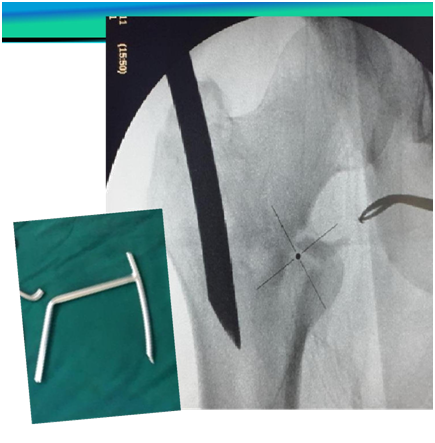

Routine and special Instruments

1. Proximal reamer

2. Internal reduction device to redirect Guide wire,

3. Sleeve with Multiple parallel holes

4. Large sleeve (Figure 5)

Figure 5 Routine and special Instruments.